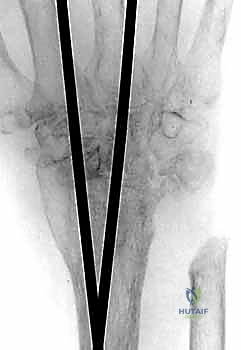

يتم استخدام شريحة معدنية خاصة (Wrist Fusion Plate)، غالباً مصنوعة من التيتانيوم، مصممة خصيصاً لتناسب تشريح الرسغ. يتم تثبيت هذه الشريحة بمسامير قوية تمتد من عظم الكعبرة في الساعد، مروراً بعظام الرسغ، وصولاً إلى العظم المشطي الثالث (Third Metacarpal) في اليد. هذا التثبيت الصلب يمنع أي حركة ويسمح للعظام بالالتحام لتكوين كتلة واحدة صلبة.

بعد التأكد من قوة التثبيت باستخدام جهاز الأشعة السينية داخل غرفة العمليات (C-arm)، يتم إعادة الأوتار إلى مكانها، وإغلاق الشق الجراحي بغرز تجميلية دقيقة لتقليل الندبات، ثم يتم وضع اليد في جبيرة أو دعامة صلبة لحمايتها.